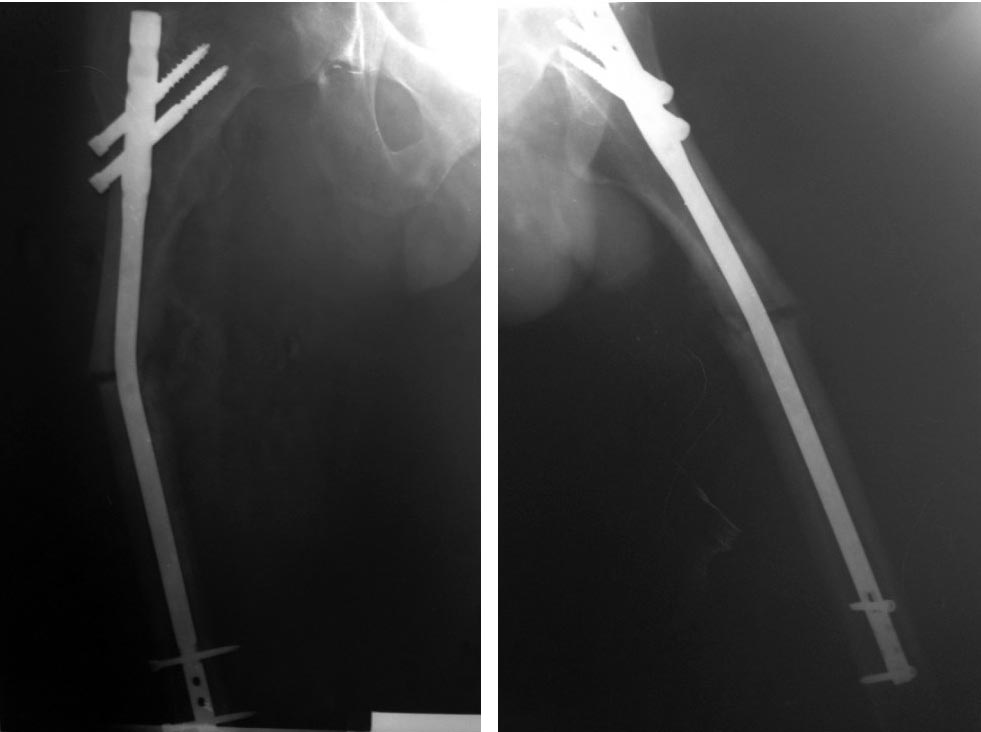

Пациент- мужчина, 25 лет, травма в ДТП 26.03.2016г., прооперирован по

поводу перелома бедра 11.04.2016г.- закрытая репозиция, БИОС стержнем

ChM 10 мм,L 320 мм. В результате повторной травмы 13.07.2016г.стержень

согнулся во фронтальной плоскости под углом 20 гр.Как удалить? Менять

способ фиксации или повторно БИОС?